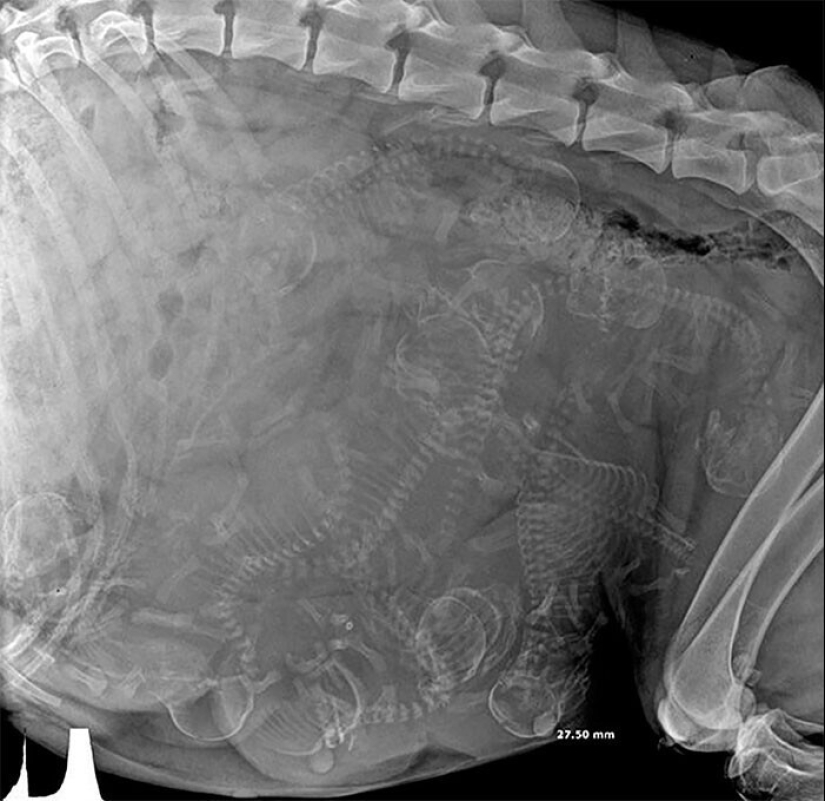

X-ray de una perra preñada

X-ray de una embarazada gato

Mujer embarazada de Python